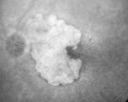

FLUORESCEIN ANGIOGRAPHY: Fluorescein angiography shows concentric geographic atrophy, predominately nasal to the fovea in each eye. The geographic atrophy is unfortunately now closer to the foveal center.